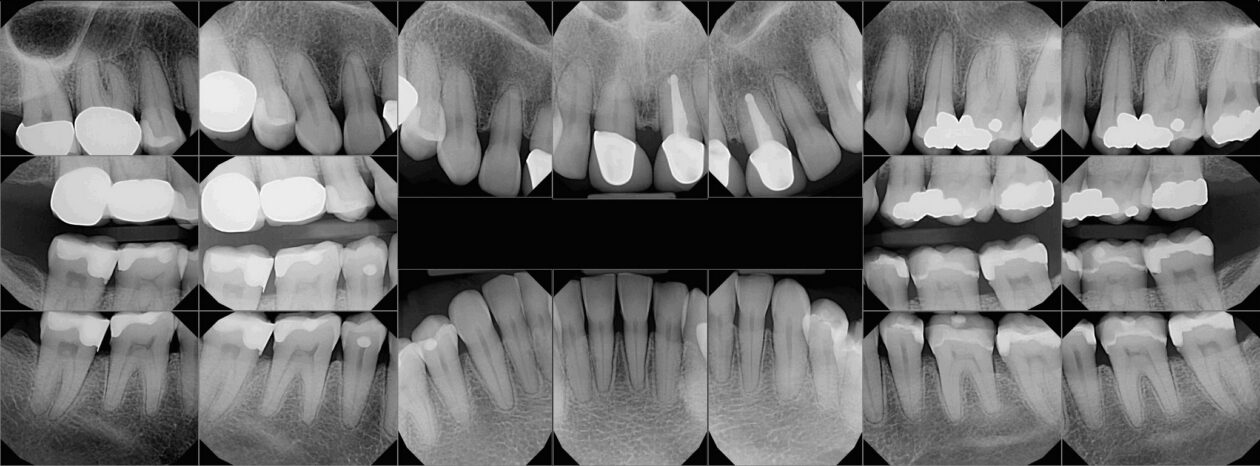

Implant restoration in the esthetic zone often requires well-coordinated interdisciplinary care in order to achieve ideal treatment results. This is especially the case when implants are planned to replace periodontally hopeless teeth. When teeth are extracted, we can typically anticipate 2mm of facial recession. If implants are to be placed following the extraction of hopeless teeth with an already existing gingival height discrepancy, the discrepancy will likely be exacerbated.

Extraction after forced eruption can allow for a much more favorable implant site compared with extraction alone. This is possible because the tension applied to the periodontal ligament during orthodontic tooth movement stimulates osteoblastic activity to induce new bone formation. As the tooth moves coronally during extrusion, soft tissue and bone attached to the periodontal fibers migrate in the same direction. As a result, forced eruption can be used to enhance the quality and quantity of both hard and soft tissue of future implant sites.

The special report presented below illustrates how orthodontic extrusion was successfully used to improve the periodontal architecture prior to the placement of two adjacent implants in the esthetic zone and thus allowed for a more ideal restorative result.